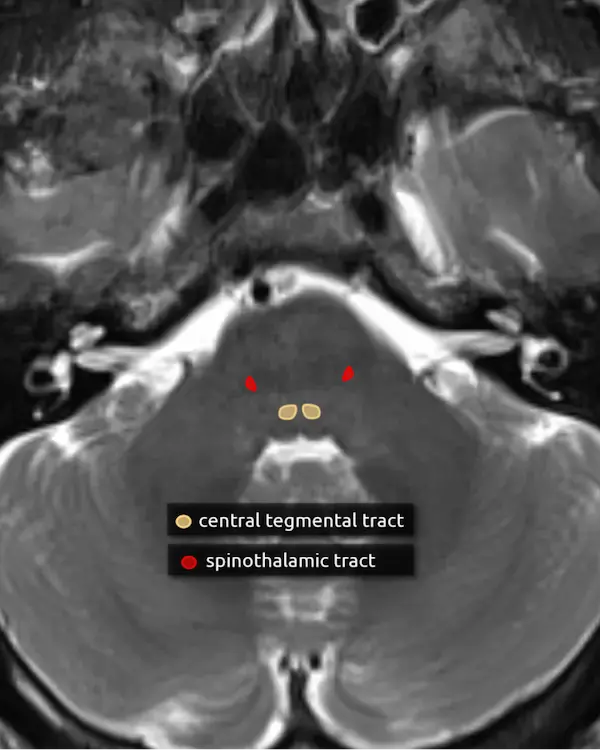

12. Spinothalamic tract

The spinothalamic tract is responsible for pain and temperature sensation. It is found throughout the dorsal brainstem adjacent to the medial lemniscus. Like the medial lemniscus, fibers terminate at the thalamic ventral posterolateral nucleus (VPL).

Fibers of the spinothalamic tract decussate in the spinal cord, so lesions will cause contralateral loss of pain and temperature sensation.

9. Central tegmental tract

The central tegmental tract extends from the midbrain to the medulla but is easiest to approximate in the dorsal pons. It connects the red nucleus to the ipsilateral inferior olivary nucleus (see the dentatorubro-olivary pathway).

Signal abnormalities of the central tegmental tract may occur with vigabatrin toxicity, which is common in children being treated for infantile spasms. Lesions here may also cause hypertrophic olivary degeneration, classically associated with palatal myoclonus.